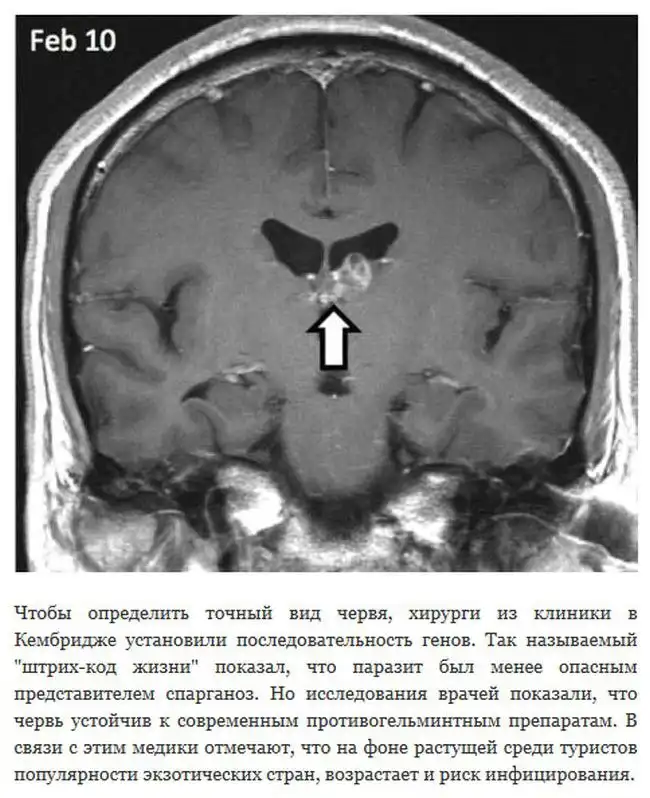

В Великобритании исследования одного пациента показали, что живущий в его мозге червь смог преодолеть расстояние в 5 сантиметров, от правого края до центра. Для того, чтобы продвинуться на такое расстояние, сантиметровому цепню понадобилось целых четыре года.